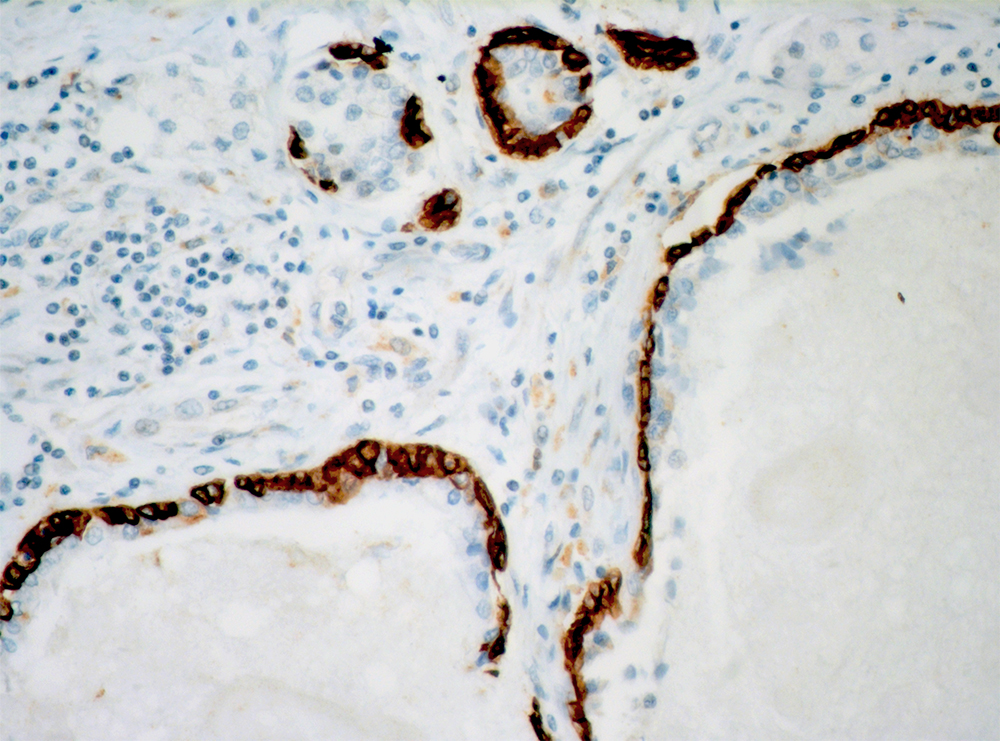

Anti-Cytokeratin 14

Keratins are intermediate filament proteins expressed by epithelial cells in cytoplasm. Mitotically active basal layers of most stratified squamous epithelia cells express 10% to 30% of their total protein as keratin. Cytokeratin 14 (CK14) is a 50-kDa keratin expressed in abundance in epidermal cells, basal cells, mesothelial cells, stratified epithelial cells, and myoepithelial cells in various tissues including prostate and breast. CK14 is helpful in the identification of breast cancer with basal phenotype